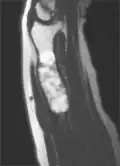

| X-ray image showing enchondromas localized in the lower part of the radius of a 7-year-old girl with Ollier disease. | |

MRI showing enchondromas localized in the lower part of the radius of a 37-year-old patient affected with Ollier disease

MRI showing enchondromas localized in the lower part of the radius of a 37-year-old patient affected with Ollier disease -